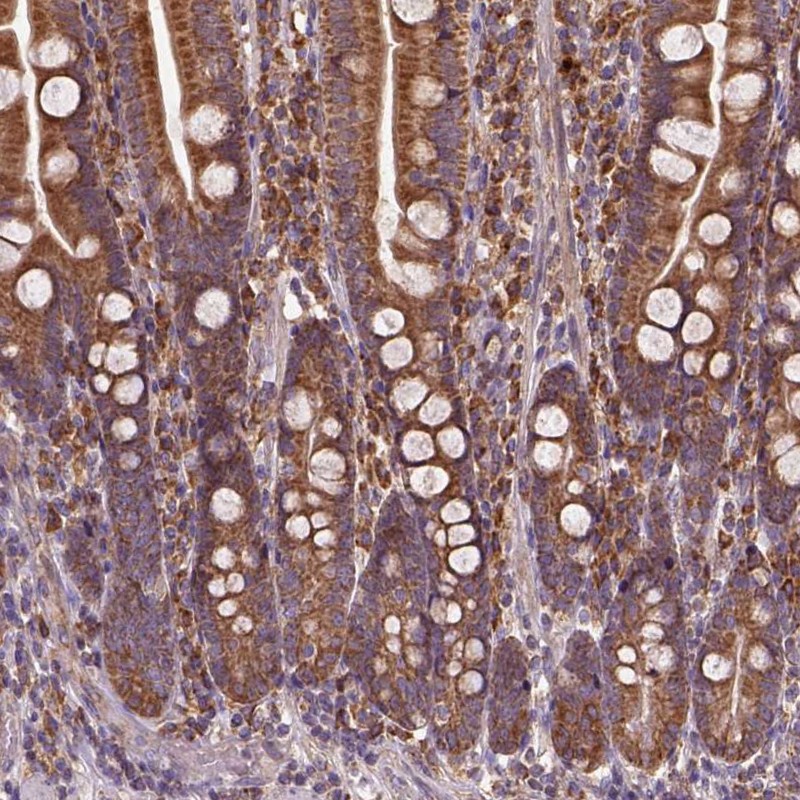

Immunohistochemical staining of human duodenum shows cytoplasmic positivity in glandular cells.